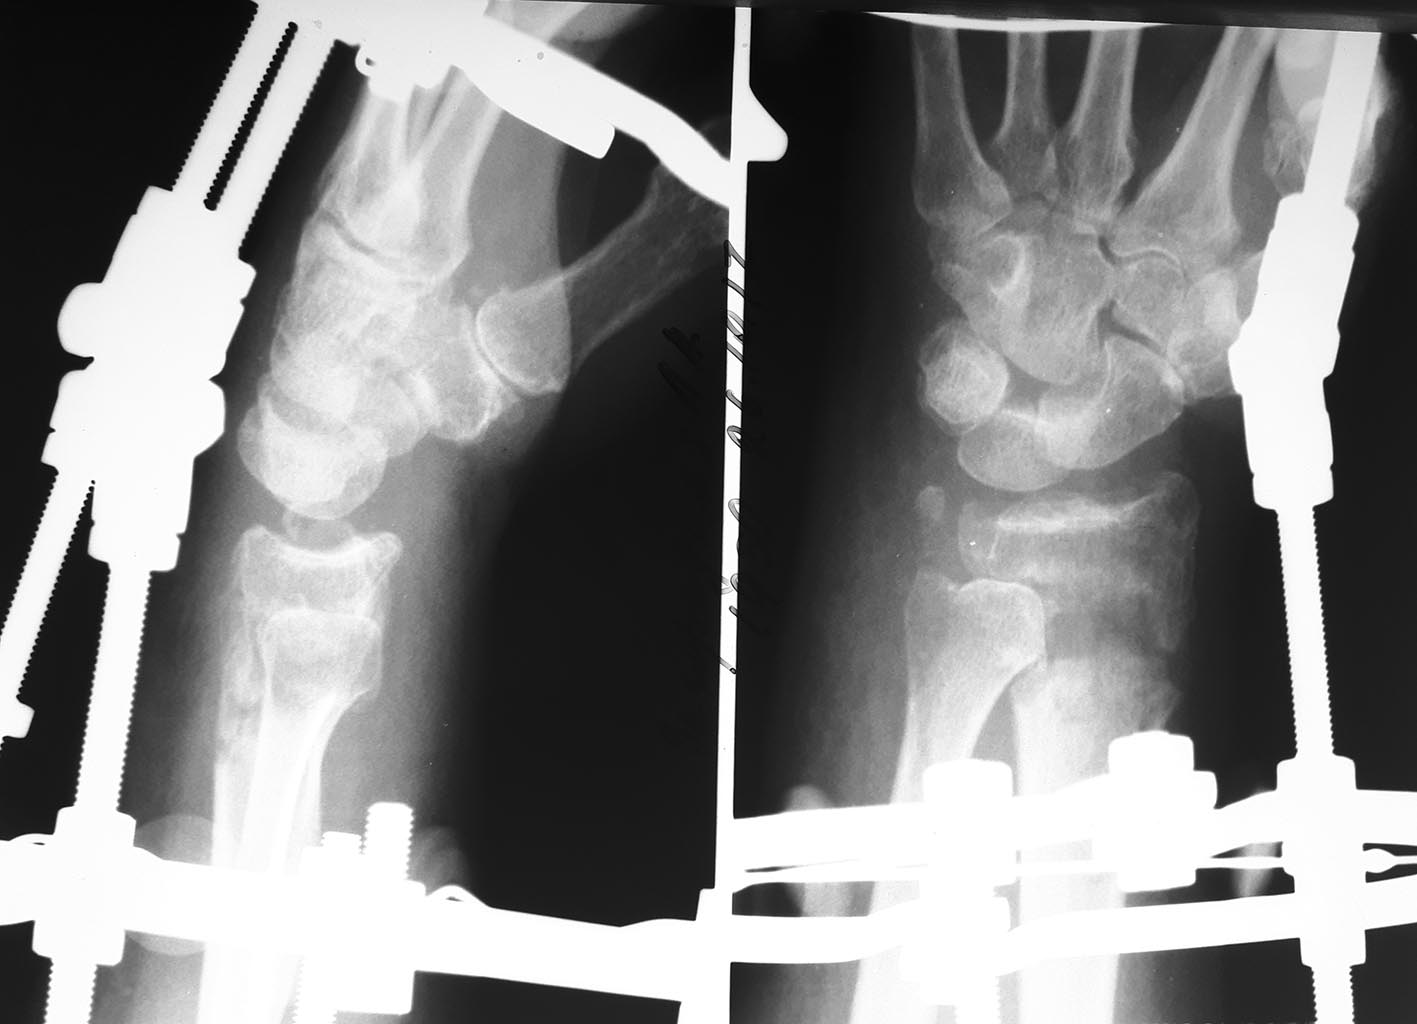

Пациентка 60 лет, 2 мес назад перелом дистального эпиметафиза лучевой

кости, шиловидного отростка, Наложен АВФ. По разным причинам продолжила

лечение у хирурга, который проводил дистракцию. Сожалею, первичные

снимки предоставить не могу. Рентген при поступлении и после "сброса"

дистракции. Сейчас думаем, что с этим делать,четкого плана пока нет,

какие у вас мысли по этому поводу?